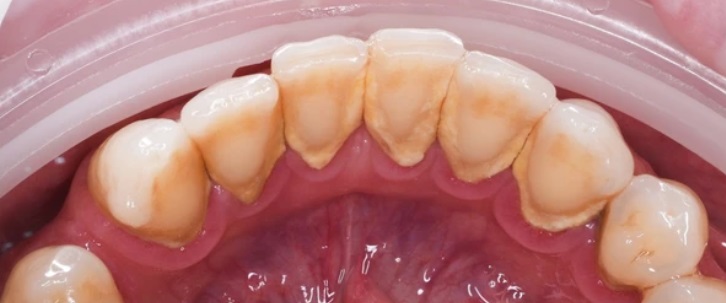

Проблема

Пациент обратился с жалобами на зубной налет, наличие зубного камня на передних зубах нижней челюсти.

Решение

Проведена профессиональная гигиена полости рта (AirFlow). Удален зубной камень и налет. Пациент доволен!